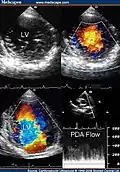

Transthoracic two-dimensional study with color and continuous wave Doppler shows left ventricular noncompaction associated with patent ductus arteriosus (PDA). [2] -

Two-dimensional parasternal and color Doppler images at the level of both ventricles that show the noncompacted:compacted wall ratio and how the color enters the intertrabecular recesses [4]